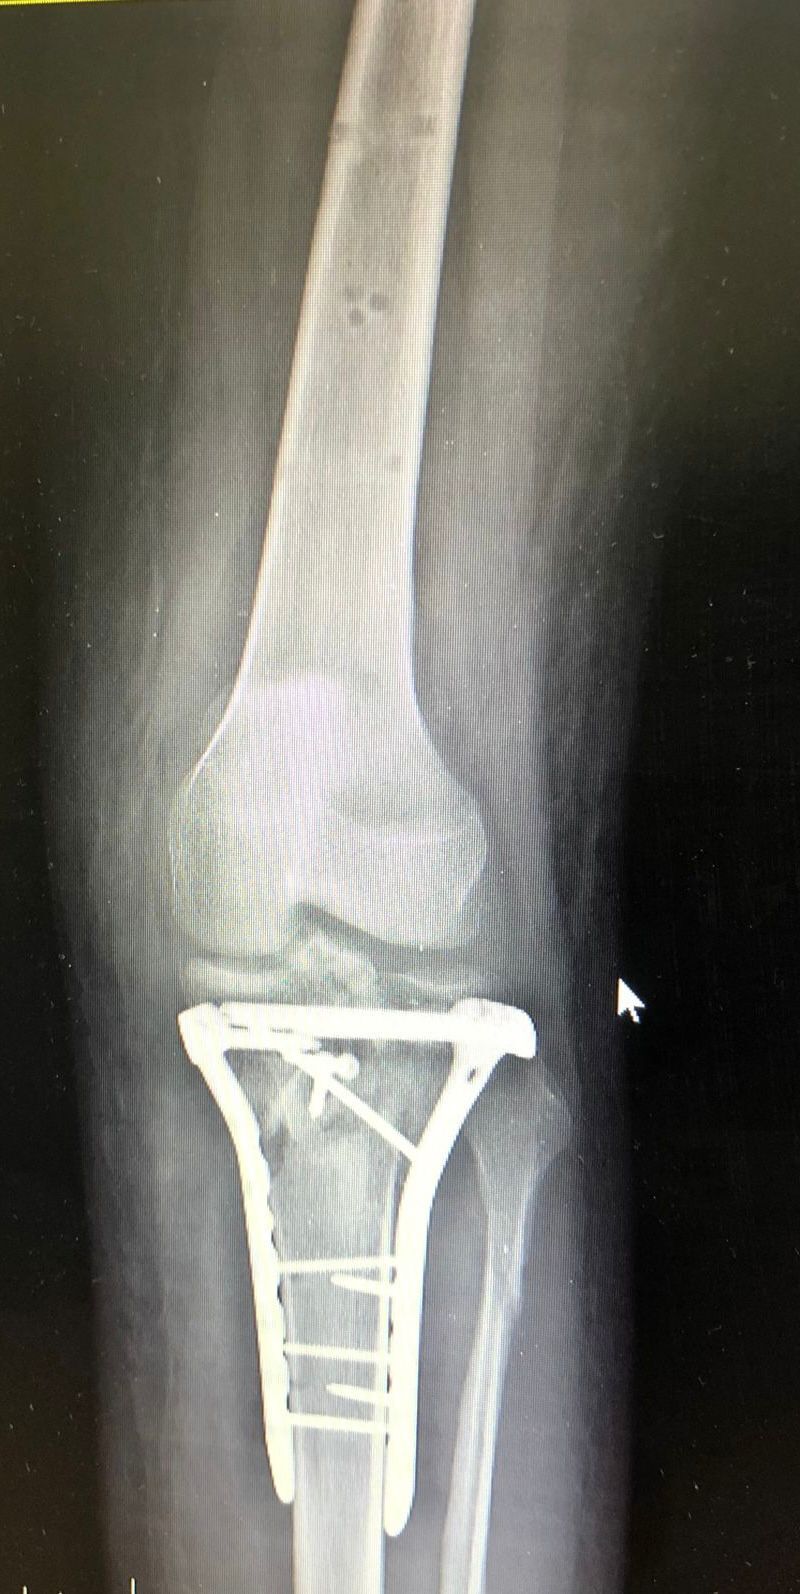

Описание снимков: На рентгенограммах левого коленного сустава в 2х проекциях: Травматических, деструктивных изменений не выявлено, структура костной ткани не изменена. Отмечается неравномерное сужение суставной рентгенологической щели в медиальных отделах-до 3.9мм,субхондральный склероз суставной поверхности там же. Межмыщелковые возвышения заострены. Остеофиты по краям мыщелков большеберцовой кости. Надколенник обычного расположения, его внутренняя поверхность уплотнена, неравномерное сужение расстояния между надколенником и бедренной костью, краевые остеофиты.Os fabella. Заключение: Гонартроз слева 2(второй) ст. по Kellgren.Пателло-феморальный артроз.

На основании 565 постановления, статьи 65-Хирургические болезни и поражения костей, крупных суставов, хрящей: диагноз: Гонартроз слева 2(второй) ст. по Kellgren.Пателло-феморальный артроз соответствует: в-В(ограниченно годен к военной службе), также при вынесении итогового заключения по категории годности, учитывается наличие и частота обращений за мед. помощью(стационарно/амбулаторно) с болевым синдромом пораженного сустава, а также эффект от проводимого лечения.